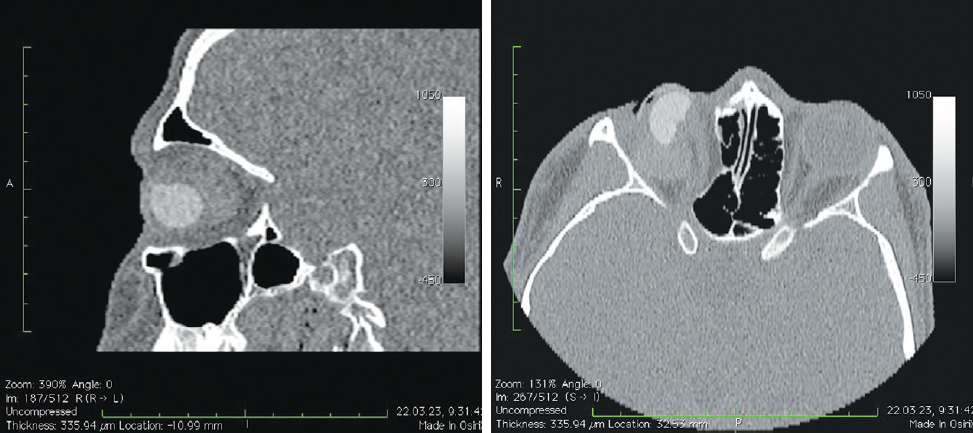

Рис. 7. Пациентка, 32 года. 3 года после операции с имплантацией эндопротеза с изменённой геометрией. МСКТ-исследование глазниц

Fig. 7. Patient, 32 y. o. 3 years after surgery with implantation of an endoprosthesis with modified geometry. MSCT of the socket

Рис. 8. Пациент, 21 год. 2,5 года после операции с имплантацией эндопротеза с изменённой геометрией. МСКТ-исследование

Fig. 8. Patient, 21 y. o. 2,5 years after surgery with implantation of an endoprosthesis with modified geometry. MSCT of the socket

При анализе рентгенологических изображений после выполнения МСКТ-диагностики у всех обследованных пациентов по описанному ранее алгоритму [16] нами было выявлено изменение размеров и геометрии орбитальных сфер в виде «срезанной» части (рис. 8). Параметры изменённой части, как и размеры самих имплантатов, были различны (табл. 1–3). Исходные параметры (диаметры) орбитальных сфер — 18, 19 и 20 мм. При компьютерно-томографическом исследовании на полученных изображениях мы анализировали размеры имплантированных материалов, определяя объём вкладышей через радиус и высоту срезанной части по формуле: V = 1/3πh2(3r – h), где π — константа, равная 3,14; r — радиус шара; h — высота шарового сегмента имплантата.

В мягких тканях вокруг изменённых имплантированных сфер нами выявлены уплотнения, без признаков кальцинации и деструкции стенок орбиты (рис. 7, 8). Кроме того, у одной пациентки было отмечено не только изменение геометрии сферы в виде срезанной части (рис. 10, а), но и наличие множества фрагментов полимерного материала идентичной рентгенологической плотности. Эти фрагменты имплантата находились за задним полюсом полимерного вкладыша в мягких тканях до вершины орбиты (рис. 10, b).